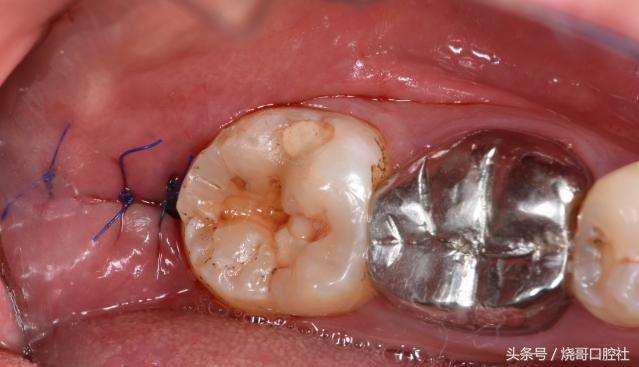

拔牙后是能够不用拆线的!比如羊肠线能够免拆,自动被牙龈组织吸收,但普通缝合线不可吸收,一般在5~7天内进行拆线处理,如果不及时拆线,要注意缝合线和牙龈长在一起,细菌会刺激牙龈发炎红肿,甚至引起口腔溃疡。

关于缝不缝线具体得看创口大小,术后较大创口都需要缝线,这样才能止血预防感染,而创口小的直接不用处理,靠血凝块自主保护,所以千万不要去破坏它,也不能吐口水。

1、食物残渣会更容易聚集在缝合线上,细菌在线周围组织滋生,感染牙龈后炎症是一回事,要害牙槽骨逐渐吸收,这才是最可怕的,因为牙龈也会跟着萎缩。